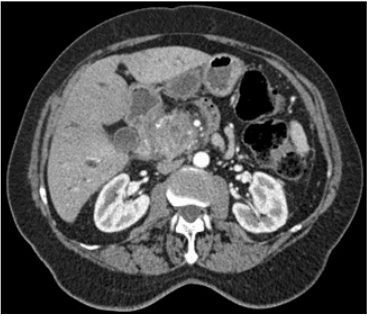

Um paciente de 55 anos de idade iniciou com quadro de icterícia, dor abdominal, colúria e acolia. Perdeu 35 kg em seis meses. Durante o processo de tratamento com quimioterapia, o paciente apresentou, após duas sessões, febre e mal-estar geral, e o hemograma do seguimento do tratamento demonstrava 75 neutrófilos e seu escore de MAASC foi de 15 pontos. A tomografia do paciente, apresentada a seguir, foi inserida para auxiliar no diagnóstico.

Considerando esse caso clínico, os conhecimentos médicos correlatos e a imagem apresentada, julgue os itens a seguir.